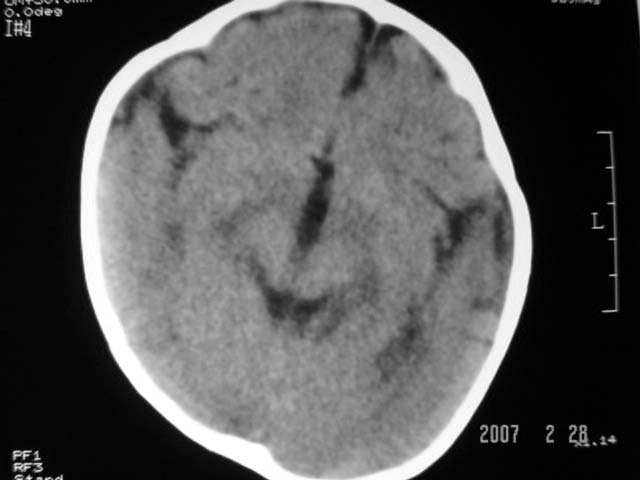

标题: PED0015:男,8M,发现不会坐立及神情异常,前囟已闭,双眼斜视,

脑回较深,白质范围小,灰白质比例失调。余未见明显异常。

考虑:脑白质发育不良,必要时请做mri进一步检查。